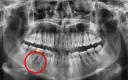

Znieczulenie przewodowe: przy większych zabiegach i zębach dolnych

Znieczulenie przewodowe jest stosowane, gdy potrzebujemy znieczulić większy obszar jamy ustnej, a także przy zabiegach w żuchwie (zęby dolne). W tym przypadku środek znieczulający podawany jest w pobliże głównego pnia nerwowego, który unerwia dany region. Blokuje to przewodzenie impulsów nerwowych na większym obszarze, co pozwala na bezbolesne przeprowadzenie bardziej rozległych procedur, takich jak usunięcie zęba mądrości czy leczenie kilku zębów jednocześnie. Efektem jest drętwienie większego obszaru, często obejmującego wargę, język i policzek.